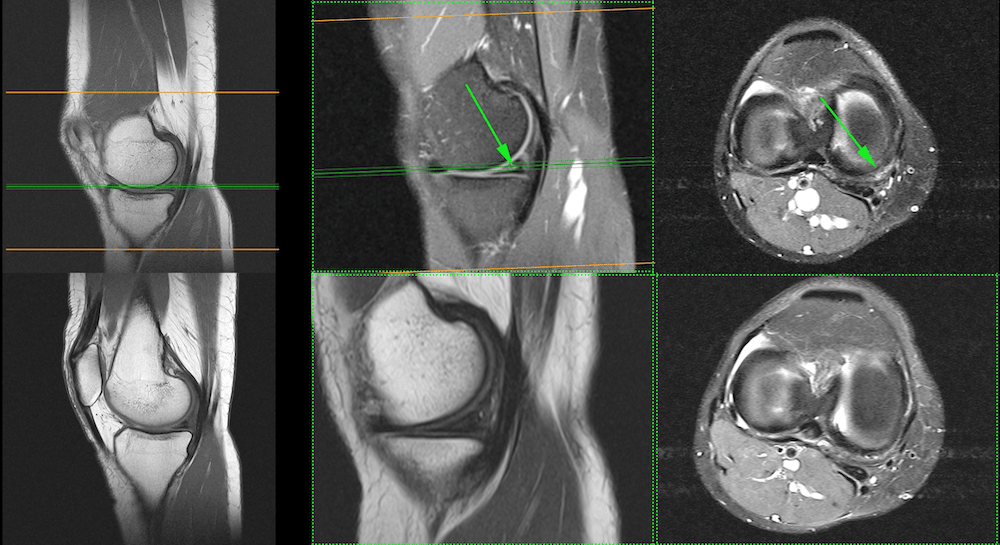

The following Magnetic Resonance Images are from Alina. The upper level shows the “before” state. A follow-up MRI a year later showed something remarkable. Not only was the torn meniscus “flat”, as would be the normal ideal outcome of conservative therapy, but it could barely be found on the MRI anymore. This is very astonishing, because meniscal tears normally don’t “heal” in adults, only in rare cases when the patient is young, the tear is near the capsule and is stitched with several weeks of complete immobilization.

Upper row: MRI before the treatment, which shows a meniscal tear. Lower row: MRI after BMC Stem Cell Treatment of meniscal tear. No other treatment was performed.